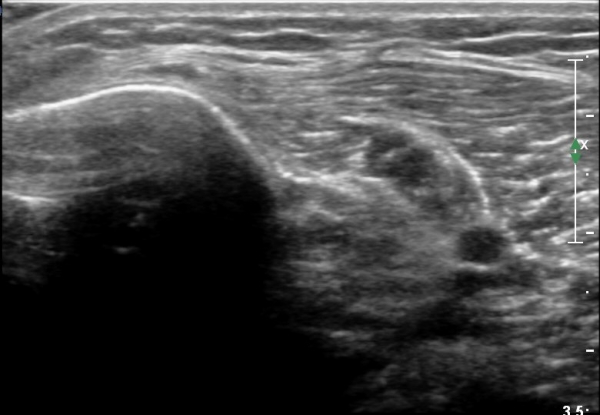

[¹«¸­] °æ°ñ ÇǷΰñÀý ÃÊÀ½ÆÄ¼Ò°ß(sonographic findings of stress fracture of tibia)

¿ìÃø ¹ß¸ñ°ú ¾Æ·§´Ù¸® ÅëÁõ(±â°£ 2ÁÖ)

±º´ë¿¡ ÀÔ´ëÇÏ¿© ÈÆ·ÃÀ» ¹ÞÀº º´·ÂÀÌ Àִ ȯÀÚ´Â ¾à 2ÁÖ ÀüºÎÅÍ ¹ß¸ñ ºÎÀ§ÀÇ ÅëÁõÀÌ ÀÖ´ø Áß

ÃÖ±Ù¿¡´Â ¹ß¸ñ À§ ¾Æ·§´Ù¸®¿¡ ÅëÁõÀÌ ¹ß»ýÇÏ°í ½ÉÇÏ°Ô °ÉÀ¸¸é ½ÉÇØÁö´Â ¾ç»óÀÓ

¾Æ·§´Ù¸® Áß°£ ºÎÀ§¿¡ °æ¹ÌÇÑ ¿¬ºÎÁ¶Á÷ ºÎÁ¾ÀÌ °üÂûµÇ°í ¾à°£ÀÇ ±¹¼ÒÀû ¾ÐÅëÀ» º¸ÀÓ.

ÃÊÀ½ÆÄ °Ë»ç

¹Ì¼¼ÇÏ°Ô ¿¬ºÎÁ¶Á÷ ºÎÁ¾°ú °¡°ñ Çü¼ºÀÌ °üÂûµÊ.

Bilateral stress fracture of the tibia diagnosed by ultrasound. A case report

https://www.ncbi.nlm.nih.gov/pmc/articles/PMC3558228/pdf/main.pdf